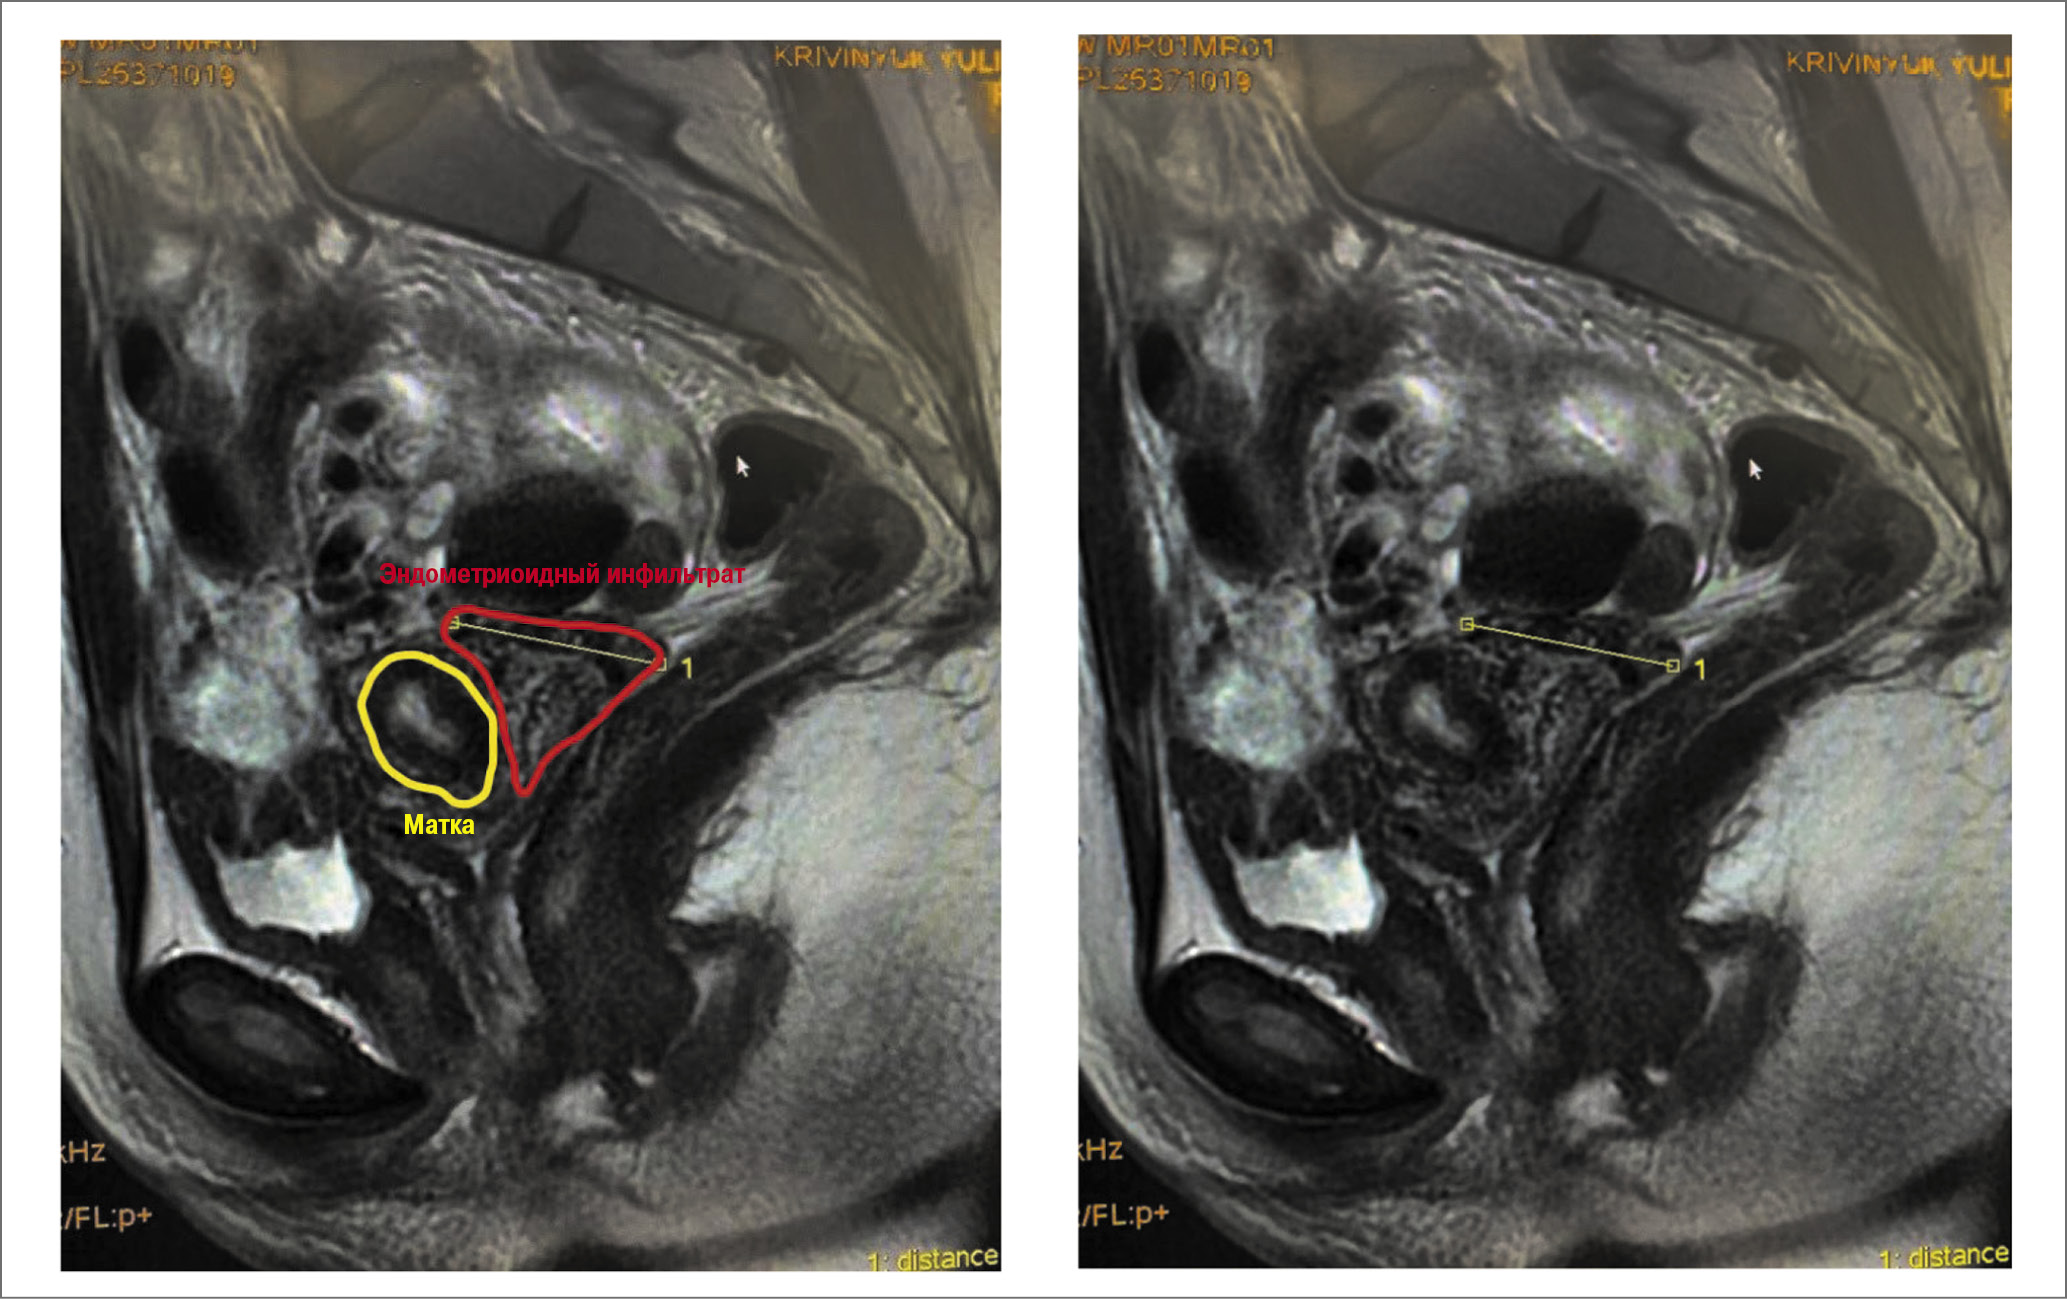

Эхографическое исследование (рис. 2) позволило обнаружить инфильтрат и описать его топографию у 49 (83,05%) пациенток, специфичность метода составила 90,76%, чувствительность – 92,45%, +PV – 89,09%, -PV – 93,65%, LR+ – 10,01%, LR- – 0,08%, распространенность – 44,92%. МРТ в 56 (94,81%) наблюдениях (рис. 3): специфичность – 93,65%, чувствительность – 90,32%, +PV – 93,33%, -PV – 90,77%, LR+ – 14,22%, LR- – 0,1%, распространенность – 49,6%.

Рис. 3. МРТ пациентки с эндометриоидным инфильтратом в клетчатке маточно-прямокишечного углубления. На уровне маточно-прямокишечного углубления в клетчатке, имеющей слабо повышенный МР-сигнал на Т2ВИ, определяются извитые участки линейной формы, с четкими контурами, имеющие повышенный МР-сигнал на Т1ВИ за счет наличия крови. Образования справа до 22×24×27 и 16×18×26 мм, слева до 53×53×59 и 14×23×24 мм в виде кист с неравномерно утолщенными стенками и четкими границами, интимно прилежащие снаружи к задней стенки шейки матки и имеющие такие же тканевые характеристики, определяются на уровне придатков. / Fig. 3. MRI of a patient with an endometrioid infiltrate in the rectouterine pouch. In the rectouterine pouch, tortuous areas of a linear shape, with sharp contours, with increased MR signal on T2WI due to the presence of blood, are detected in the tissue with slightly increased MR signal on T1WI. At the appendages level, cyst-like masses up to 22×24×27 mm and 16×18×26 mm on the right and up to 53×53×59 mm and 14×23×24 mm on the left with irregularly thickened walls and sharp contours, intimately adjacent to the posterior cervical wall and having the same tissue characteristics, are observed.